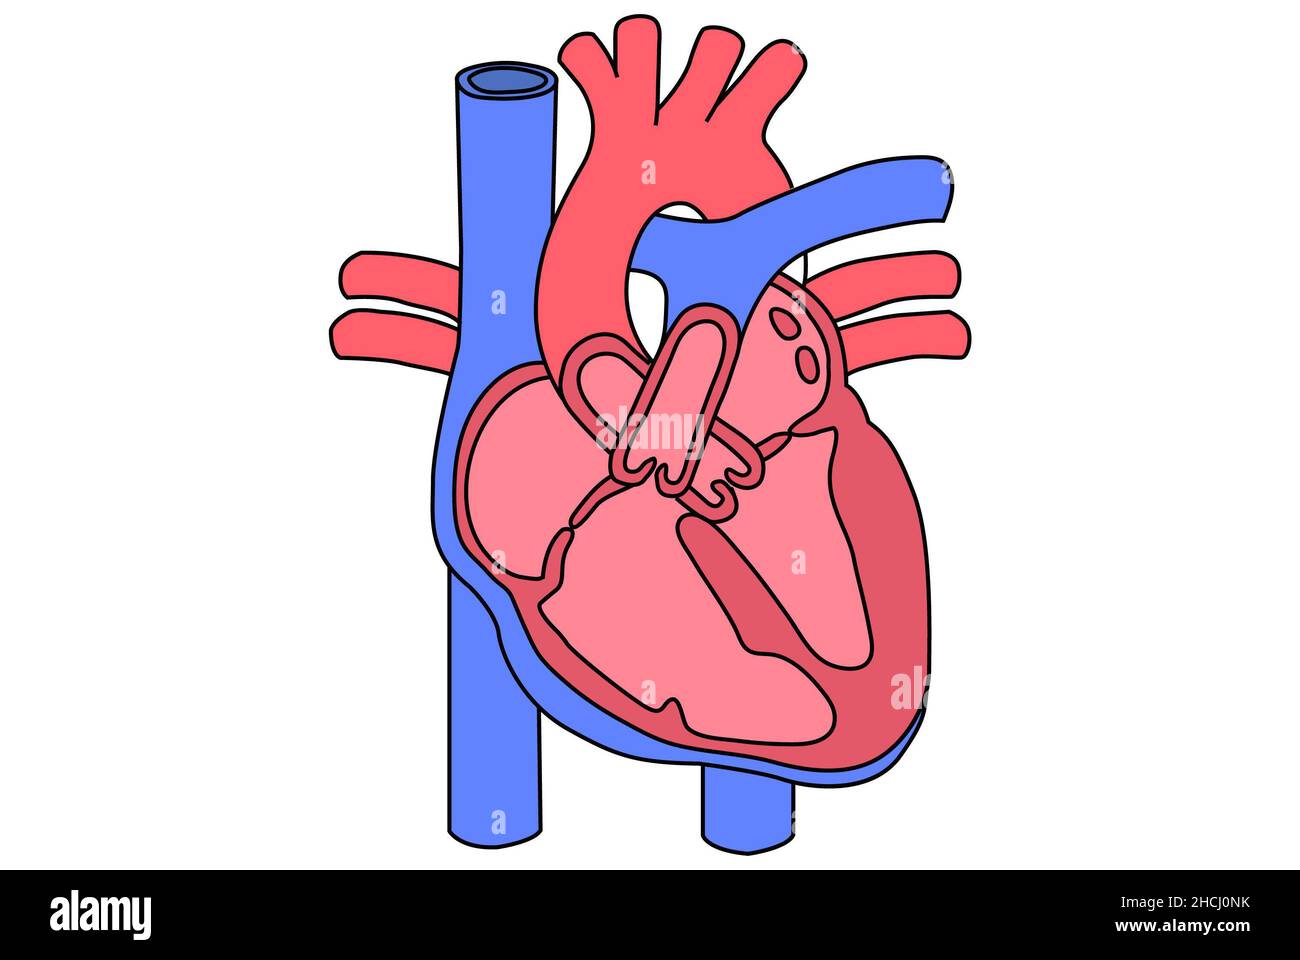

Diagram of a hart, basic heart anatomy. Stock Photohttps://www.alamy.com/image-license-details/?v=1https://www.alamy.com/diagram-of-a-hart-basic-heart-anatomy-image455241183.html

Diagram of a hart, basic heart anatomy. Stock Photohttps://www.alamy.com/image-license-details/?v=1https://www.alamy.com/diagram-of-a-hart-basic-heart-anatomy-image455241183.htmlRF2HCJ0NK–Diagram of a hart, basic heart anatomy.